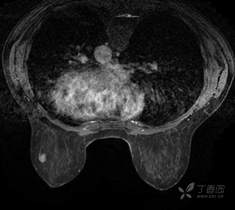

乳腺动态增强MRI 对比剂(钆布醇)

T2WI脂肪抑制序列

T1WI平扫脂肪抑制序列

DWI

T1WI增强早期

T1WI增强晚期

乳腺MR:左乳外上象限见T2WI高信号肿块影,大小约12mm×10mm×13mm,肿块为卵圆形,边缘模糊不规则;内部强化略不均匀;TIC曲线初始相呈快速强化,延迟期呈平台型;DWI呈高信号,ADC值为 0.000698 mm2/s。

因肿块边缘不规则,内部强化不均匀, TIC曲线初始相呈快速强化,延迟期呈平台型;DWI呈高信号,ADC值较低,考虑左乳外上象限肿块恶性不除外,BIRADS 4类。